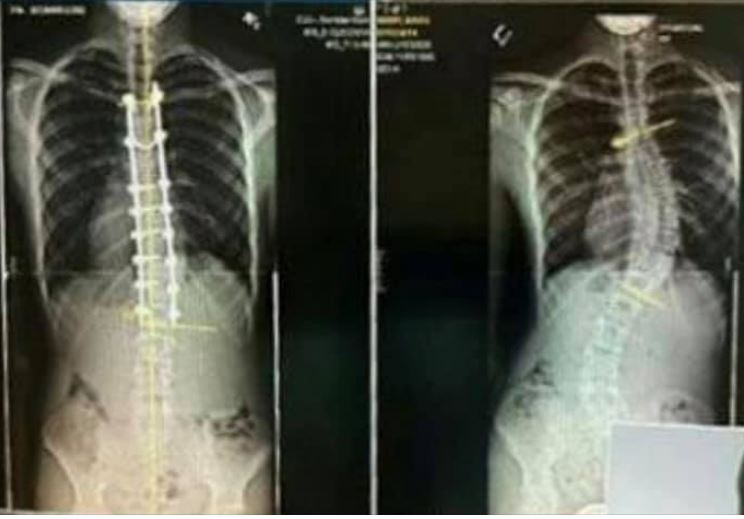

Another example. When my son Davis was around 14 1/2 he was diagnosed with scoliosis. His initial spine curvature was 19 degrees and we hoped to all hopes we could manage with a physical brace. But as he grew his curve got disastrous, to the point it was going to require surgery. And while I tried my best to be the “strong Dad” for Davis in his presence, I was so upset and at one point told God himself that “This isn’t FAIR!” But it had nothing to do with fairness. My son had scoliosis. End of story.